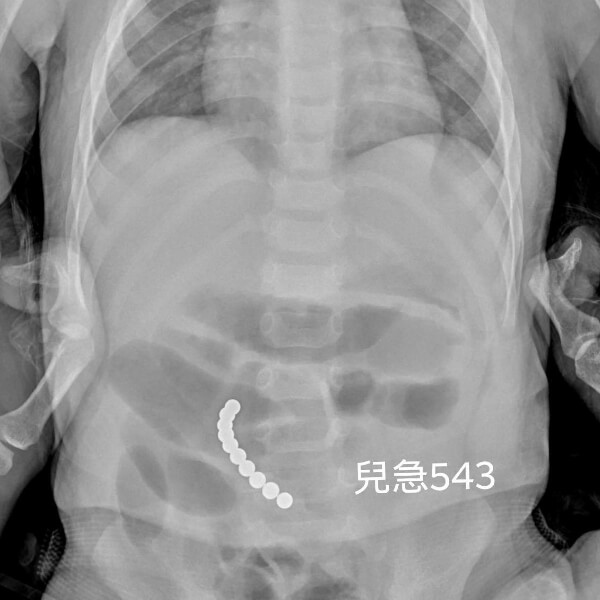

儿科急诊医师近日,在脸书粉专分享一名急诊案例,一名男童因连续呕吐3天(每天分别吐了5~6次),前来儿科急诊就医。...